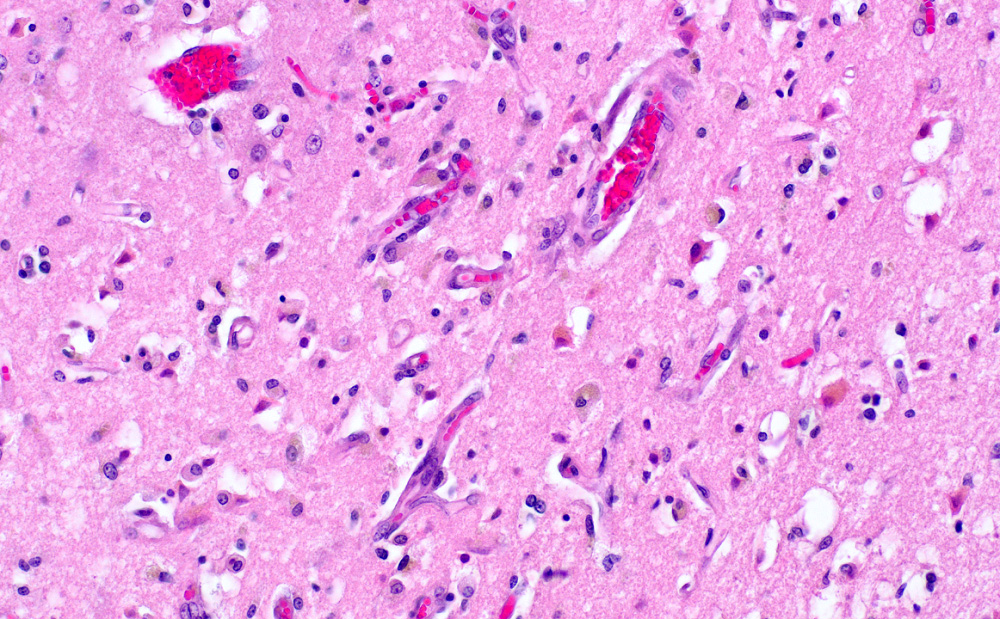

- Subacute (5 - 14 days)

- Dense macrophage infiltration and scattered siderophages

- Variable neutrophilic infiltration

- Peripheral reactive astrocytosis and microglial activation (i.e., rod shaped microglia)

- Hypereosinophilic neurons are still present in gray matter

- Neovascularization of necrotic tissue and reactive endothelial cells

- Chronic (15 days - years)

- Cavitated lesion with vessels and macrophages surrounded by a glial scar

- Reactive astrocytes in the edge of the cavitation

- Scattered hemosiderin laden macrophages typically present

- Axonal balloons can occur in all phases of ischemic injury (i.e., dilation of axons indicate injury with subsequent defective axonal transport)

- Neuronal ferrugination occurs occasionally in subacute to chronic infarcts, characterized by perykaryal mineralization (i.e., prominent basophilia)

Microscopic (histologic) images